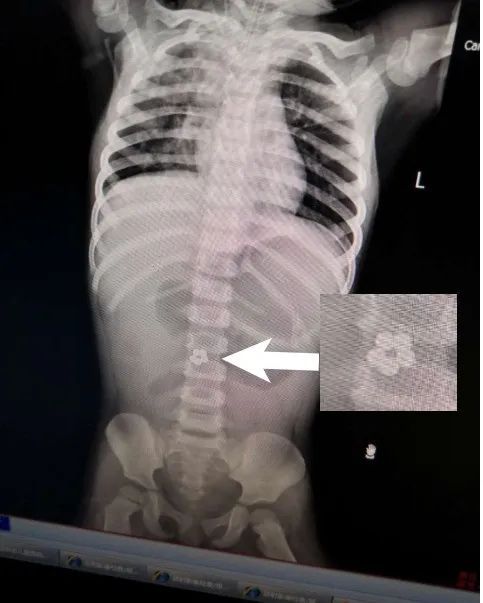

眼见治疗没效果,医生让孩子拍片检查。这一查——

在小静肚子里

居然发现

有5个连成圈的小球!

X光检查发现,小静腹中有5颗小球。

看完片子,妈妈后背一阵发凉:“这些小球……怎么像是之前买的玩具?”

2018年1月,深圳18个月大的小安(化名)不知道啥原因反复呕吐。就这样过了一周,孩子的精神逐渐变差。心急如焚的爸妈把孩子带到深圳市儿童医院,并做了个腹部X光检查,结果发现,小安的肠道内居然有5颗连在一起的圆珠子!